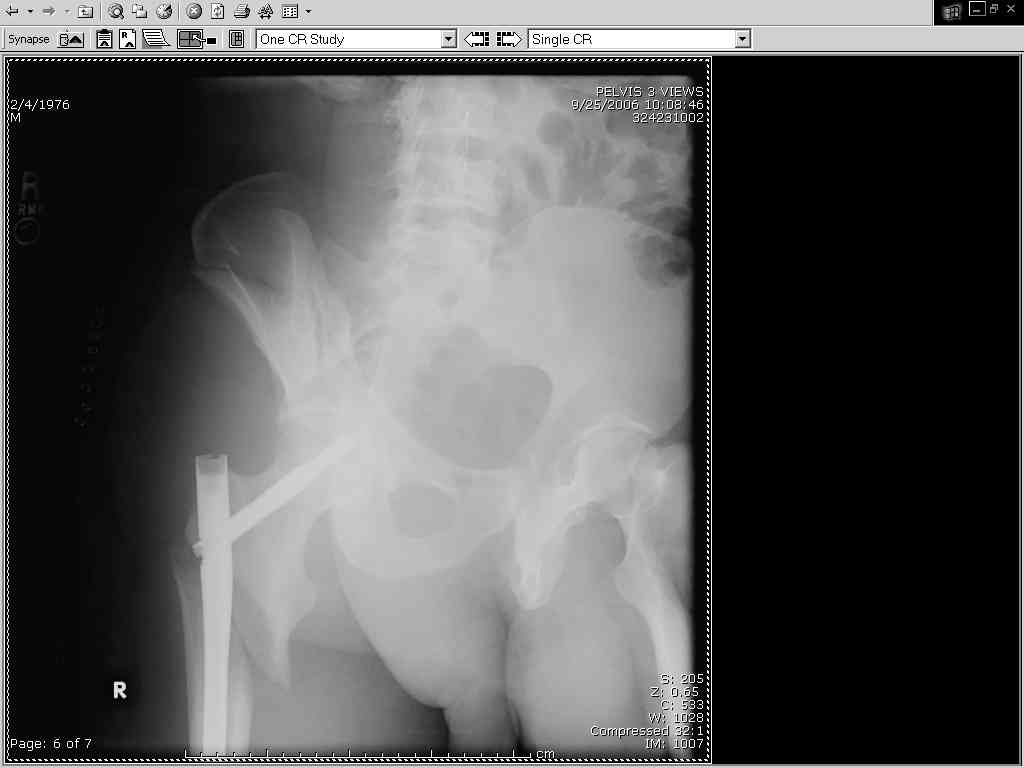

Thanks Adam - I agree it's not a pure APC (is there really such thing as a pure force vector strictly in the x,y or z plane?). I stand corrected. Maybe a hybrid APC (ext rot of L hemipelvis, symphysis disruption, ext rot of R anterior innominate) plus vertical shear as well with 3 or-so cm of cephalad migration of the R ilium. Maybe just "C-type".....

It almost looks to me like an extra-articular both column fx, in addition to the pelvic component. It has the typical triangular fragment and the OO view has a hint of the spur. You may be able to get it all with plates. I would consider fixing the crest first, then a long plate for both symph and iliac portion. SI may close with reduction of symphisis. Looks like the inferior portions are intact. I like your plan as well. You will probably solicit lots of opinion. Good luck. Look forward to post op view.